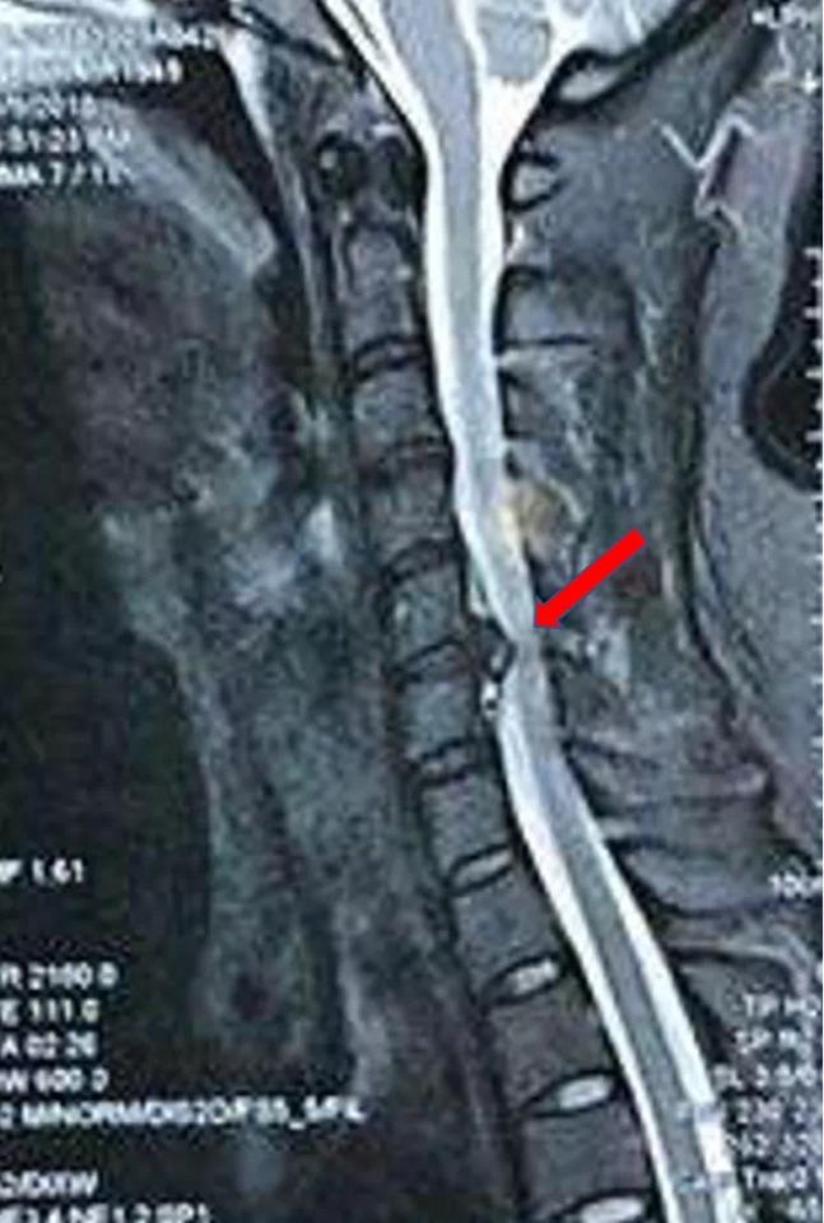

Jul 25, · 颈椎压迫了神经,要看它压迫的部位以及压迫的程度。通过核磁检查,就能发现,再看椎间孔位。 如果它的突出非常大,把椎间孔的神经压的非常死的话,而且经过保守治疗没有效的话,建议手术治疗,因为它突出的太多,已经把神经根已经压的丧失功能了。Jun 07, 17 · 颈椎病压迫脑神经的症状有哪些 1 症状一:主要有颈背疼痛、上肢无力、下肢乏力、手指发麻、行走困难、头晕、恶心、呕吐,甚至视物模糊、心动过速及吞咽困难等。 颈椎病的临床症状与病变部位、组织受累程度与个体差异有一定关系。 2 症状二:交感Sep 10, 19 · 颈椎压迫神经首先要解决症状,可以使用消除水肿、营养神经、改善循环等药物,改善神经压迫症状。对于有合适适应症的患者,可以进行颈部牵引。对于合并有疼痛、手麻的患者,进行针灸、推拿、拔罐、理疗的治疗。对于情况严重患者且符合手术指征,可行手术治疗。

May 30, 19 · 先到医院做颈椎磁共振检查,了解神经受压的程度、神经受压的范围和神经受压的部位。如果神经受压不严重,一般先进行保守治疗,包括牵引、按摩、理疗、针灸、拔罐、止痛活血药物治疗等。90%的患者通过保守治疗可明显缓解手麻的症状。如果神经受压非常严重,在保守治疗效果不好的情况下,建议进行手术治疗。有些人担心颈椎病手麻及无力是不是要瘫痪了,颈椎病Feb 25, · 颈椎压迫神经要区分是压迫的外周神经还是中枢神经系统。治疗方法有保守治疗和手术治疗两种。1、如果是神经根导致的上肢麻木疼痛,放射性疼痛,首选保守治疗。经过正规的保守治疗,比如针灸、按摩、药物、休息、理疗等能取得很好的效果。Oct 29, 18 · 问:颈椎压迫神经引起手麻,我老婆吃了一个老中医开的6付中药,没什么好转,他建议去医院挂神经科检查一下,他认为可能是两路神经动脉相碰到一起,才出现手麻,他说神经动脉碰一起可做微创手术,是真的吗,那这样的微创手术大概需要多少钱呢(女,48岁) 答:您好请问检查过吗?